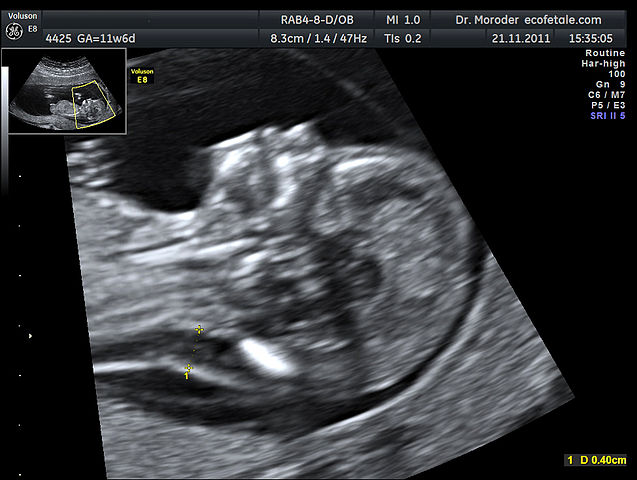

English: Ultrasound image of measurements of fetal nuchal translucency, and absent nasal bone at 11 weeks of pregnancy. CVS demontrated a trisomy 21 of the fetus

Deutsch: Erhöhte Nackentransparenz und fehlendes Nasenbein bei Fetus mit 11 Schwangerschaftswochen. Die Chorionzottenbiopsie zeigte eine Trisomie 21